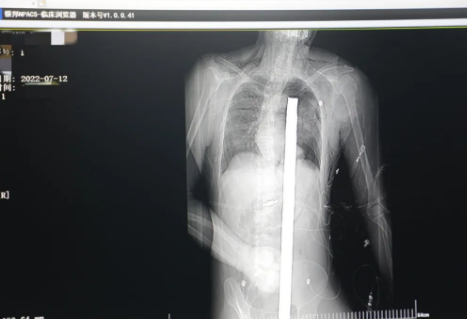

突發(fā)!太疼了,1.2米長(zhǎng)的螺紋鋼從男子會(huì)陰部垂直穿入胸腔......7月12日下午16時(shí)10分,西安一處工地的一名26歲工友,不慎從10多米的高空墜落,不幸的是工地上一根直徑3厘米的螺紋鋼從男子會(huì)陰部垂直穿入體內(nèi),工地上的工友們小心翼翼地將連著的鋼筋截?cái)唷G闆r危急,立即送往西安國(guó)際醫(yī)學(xué)中心醫(yī)院急救中心,此時(shí)正是下午17時(shí)00分。

時(shí)間就是生命!此時(shí),西安國(guó)際醫(yī)學(xué)中心醫(yī)院展開(kāi)了一場(chǎng)與生命賽跑的搶救,第一時(shí)間開(kāi)辟綠色通道,急診X光片及CT顯示:異物經(jīng)會(huì)陰部貫穿盆腔、腹腔到達(dá)左側(cè)胸腔主動(dòng)脈弓水平。醫(yī)院創(chuàng)傷中心立即啟動(dòng)應(yīng)急預(yù)案,劉延彤副院長(zhǎng)親臨指揮,下午17點(diǎn)48分,當(dāng)患者被送達(dá)手術(shù)室,胸外、心外、肝膽外科、胃腸外科,泌尿外科及麻醉科等多學(xué)科專家聯(lián)手對(duì)這名工友進(jìn)行“縱劈胸骨 前外側(cè)開(kāi)胸探查 氣管及主支氣管修補(bǔ) 肺修補(bǔ) 血胸清除 開(kāi)腹探查止血 腹膜后及盆腔探查......”手術(shù)。

情況緊急!術(shù)中探查后發(fā)現(xiàn),長(zhǎng)120cm直徑3cm的螺紋鋼經(jīng)患者右側(cè)會(huì)陰部穿入,傷及直腸,途徑膀胱后方,左側(cè)髂總動(dòng)靜脈之間傷及左腎后,經(jīng)胰腺后方在肝脾之間穿破膈肌,在下肺靜脈前方穿入左肺穿破氣管及左右主支氣管膜部,止于主動(dòng)脈弓下水平,穿入體內(nèi)的部分達(dá)到75cm。